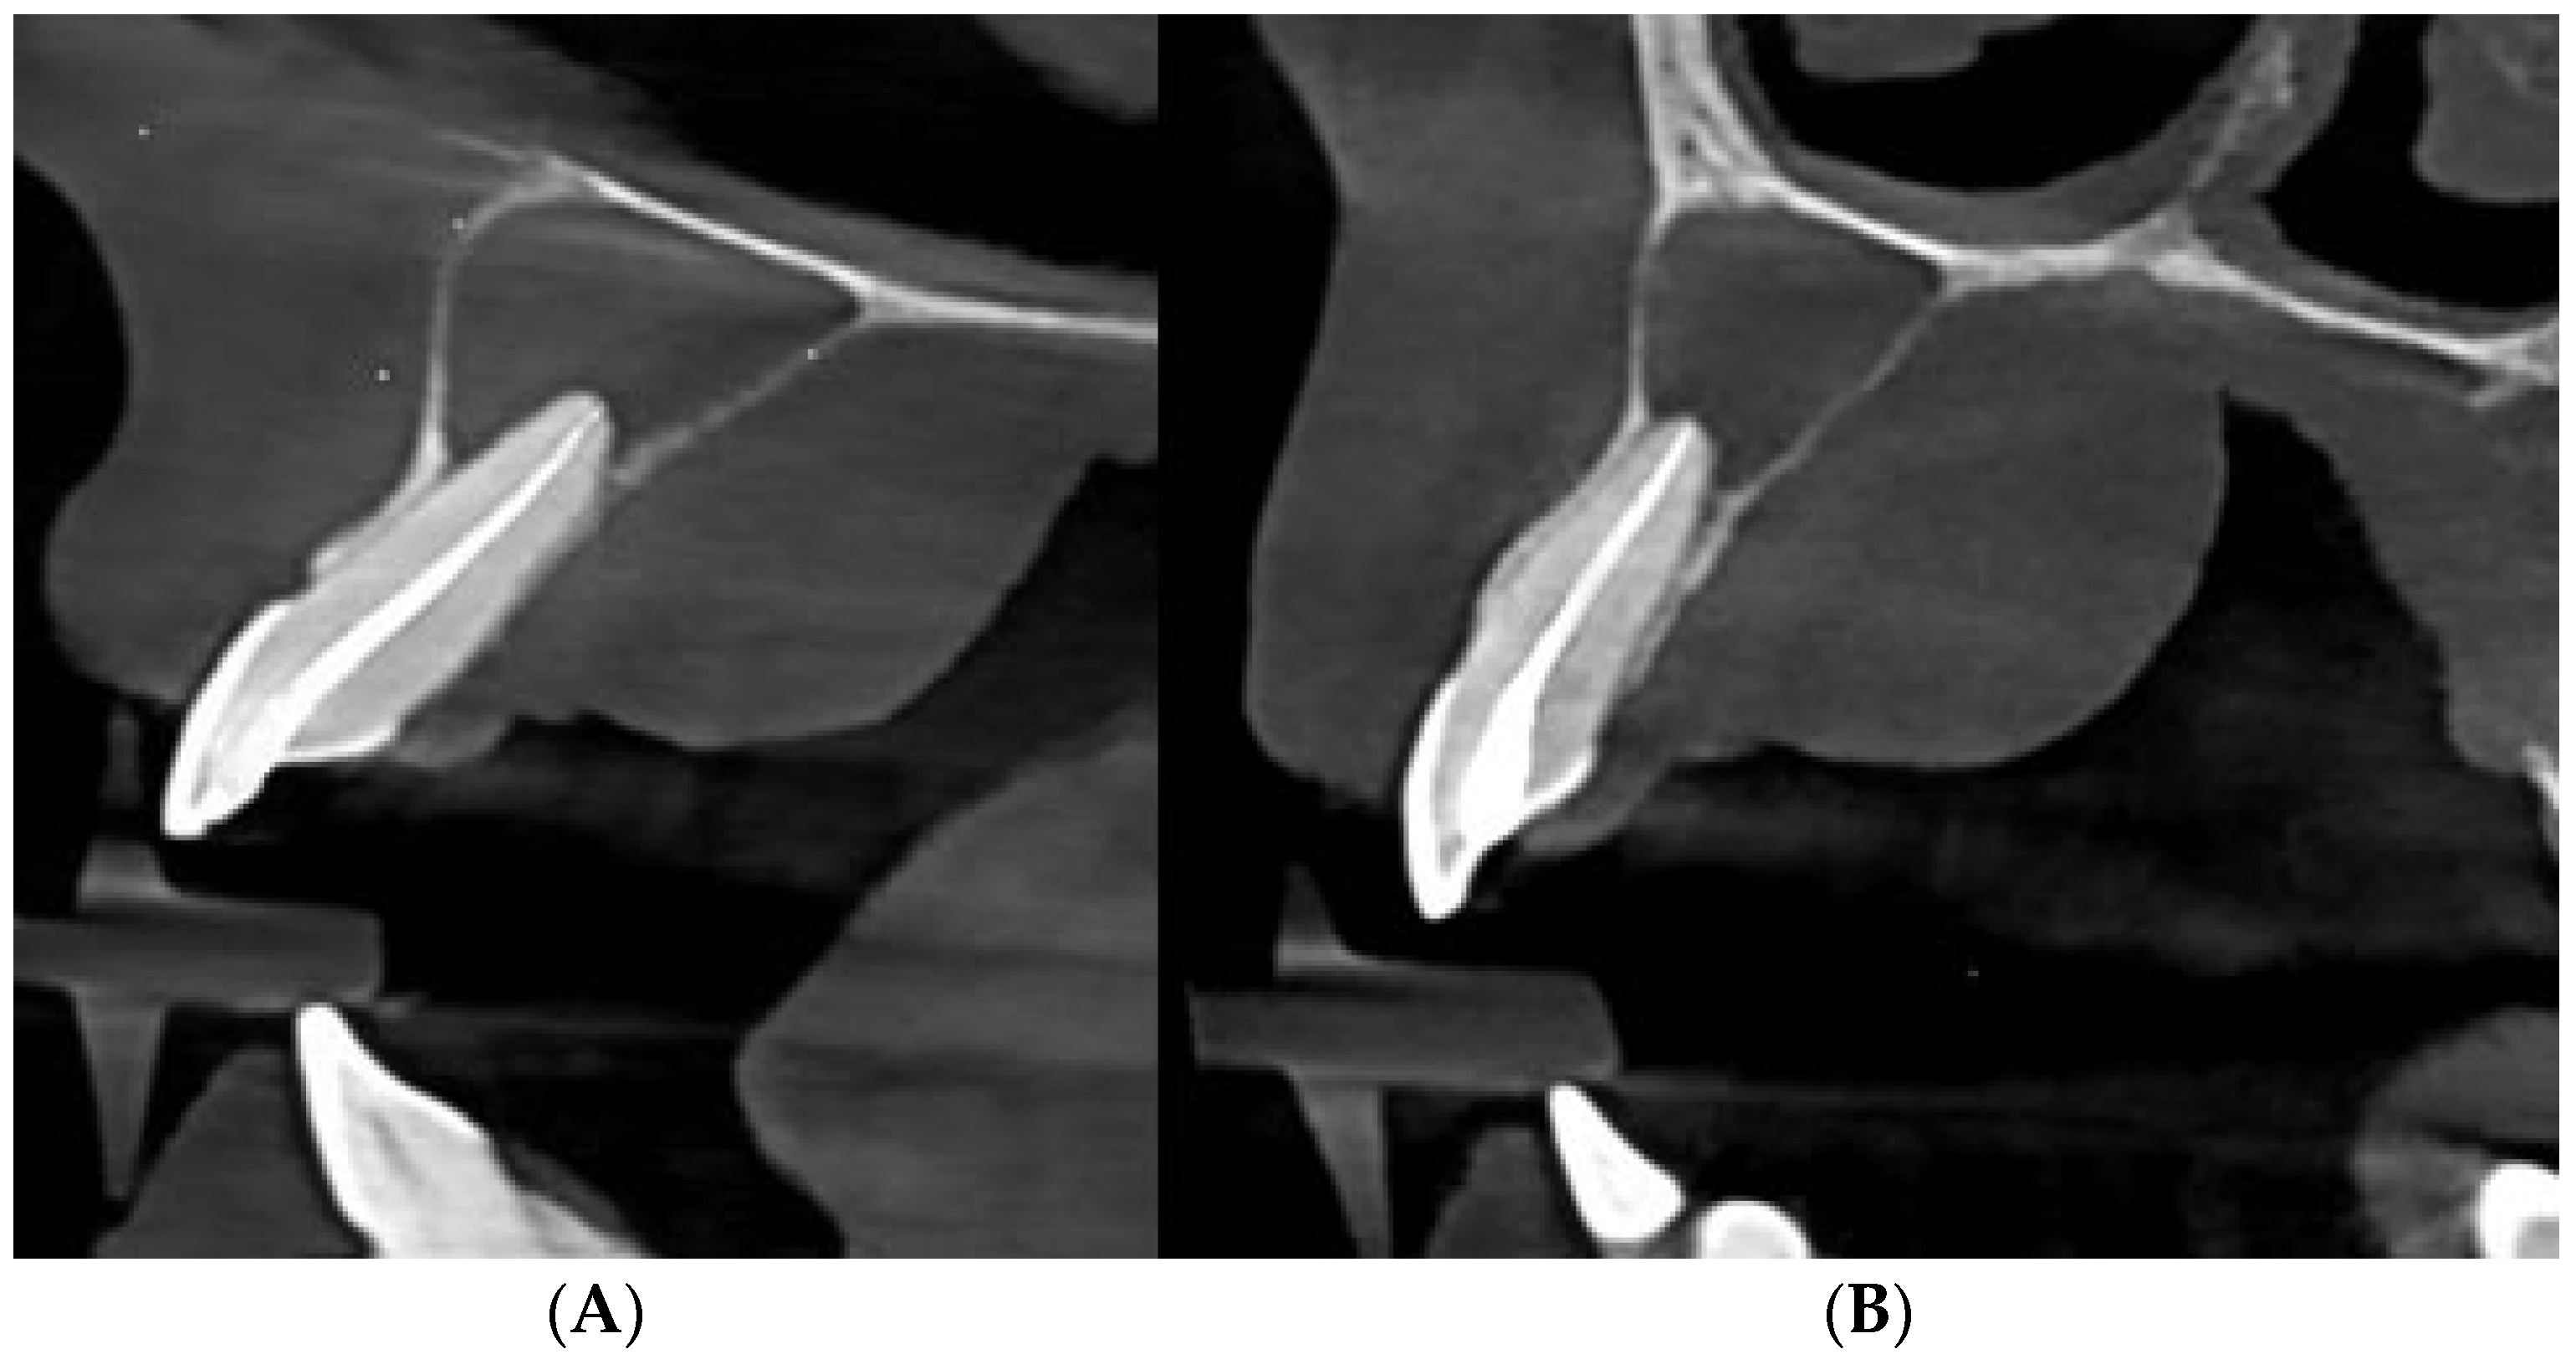

Palatal Abscess of Endodontic Origin with Extensive Radiolucency in Maxillary CBCT Imaging

Marian, D.; Constantin, G.D.; Stana, A.H.; Lile, I.E.; Hajaj, T.; Gag, O.L. Palatal Abscess of Endodontic Origin with Extensive Radiolucency in Maxillary CBCT Imaging. Diagnostics 2025, 15, 2195. https://doi.org/10.3390/diagnostics15172195